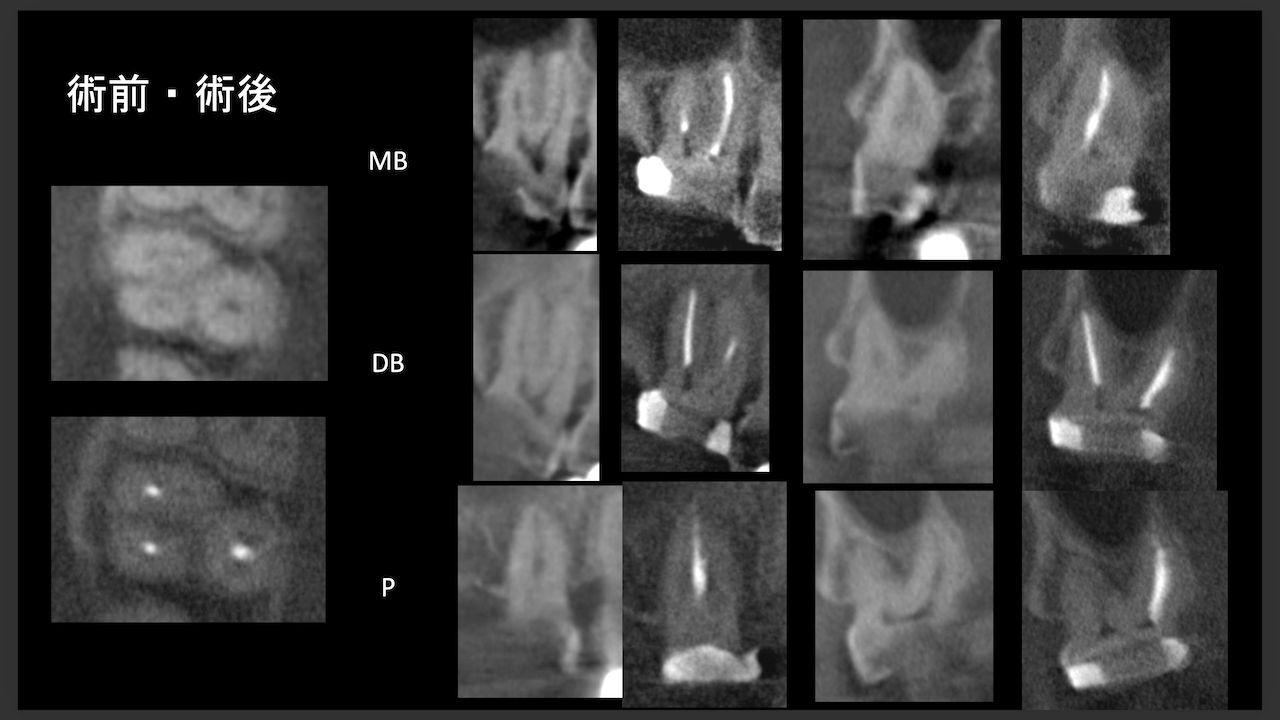

術前にCBCTを撮影したので、MB2がないということを分かった上で根管治療を行っている。

これがCBCTを歯内療法に用いる最大の利点だろう。

上手い!